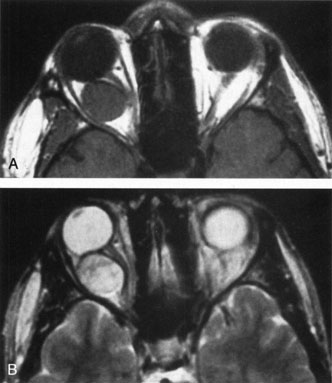

Most capillary hemangiomas can be diagnosed readily by clinical inspection. However, if delineation of the extent of deep orbital involvement is required, or the diagnosis is unclear, magnetic resonance imaging (MRI) with surface coils, gadolinium–pentetic acid enhancement, and fat suppression (to detect enhancement against the orbital fat) is indicated. The tumor is isointense to muscle and gray matter on T1- and hyperintense on T2-weighted images.22 The enhancement seen with intravenous contrast varies from moderate to intense and may be homogeneous or inhomogeneous.10 Lesions undergoing involution are less intense and more inhomogeneous. Major feeding vessels appear as black, serpiginous structures because of the “flow void” phenomenon.22 B-scan ultrasonography shows a smooth, lobular, or irregular mass with variable internal reflectivity that blends into surrounding orbital structures.23 A-scan ultrasonography shows alternating high internal reflectivity (high echo spikes) and low internal reflectivity (low echo spikes) resulting from the variable architecture and acoustic interfaces of vascular spaces, cellular areas, and septa, and moderate sound attenuation.24 High vascular flow may be demonstrated on Doppler echography. On computed tomography (CT) scan, the margins of deep infantile hemangiomas vary from moderately well defined to irregular.25 They can occur anywhere within the orbit and may be both intraconal and extraconal. There are no calcifications within these lesions. Occasionally, they indent the globe and are associated with bony orbital enlargement without erosion.10 Very rarely, angiography may be needed in the unusual situation where hazardous superselective embolization is used for life-threatening hemangiomas unresponsive to other therapies.20 These lesions frequently have multiple feeding vessels from both the internal and external carotid arteries.